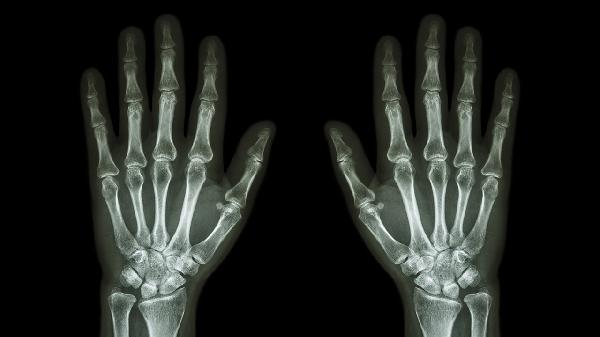

手腕三角骨疼痛可通過(guò)休息制動(dòng)、冷敷熱敷、藥物治療、物理治療、手術(shù)治療等方式緩解。三角骨疼痛可能與外傷、慢性勞損、關(guān)節(jié)炎、腱鞘炎、骨壞死等因素有關(guān)。